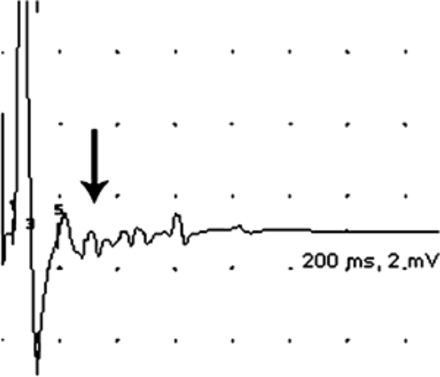

史的一个50岁的女人转移性恶性胸腺瘤出现弥漫性神经性疼痛包括化疗和放疗前四肢和躯干。她还开发情景腹泻、发汗、发烧、失眠、脑病。检查发现荡漾的肌肉(视频首页神经病学®网站www.首页neurology.org)。长期afterdischarges被发现在运动神经的研究中,神经兴奋过度的暗示(图1和图2)。肌电图(大约8年后纵隔辐射)显示束状,紧身衣,三胞胎,myokymic排放。升高血清抗体对电压门控钾通道(0.30 nmol / L,正常< 0.02)和striational肌肉(1:30,720,正常<一60)暗示多种Morvan综合症,其中包括所有的功能在我们的案例中指出。1,2Morvan综合症的中枢神经系统功能区分从艾萨克综合症,这通常是由于自身免疫性病因。大部分Morvan综合症病例是多种的,其中大部分是由于胸腺瘤。1